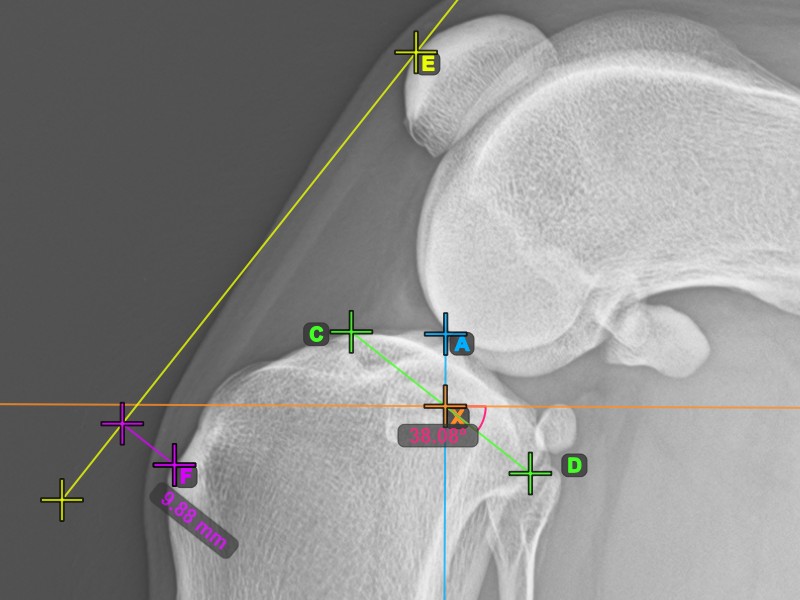

Start the TTA measurement procedure by marking the most cranial point of the Patella.

The image below depicts the usual placement of the most cranial point of the Patella.

To complete the TTA measurement procedure mark the most dorsal point of the Crista Tibiae (Tuberositas Tibiae). The distance between the Tuberositas Tibiae and the line passing along the most cranial point of the Patella is the required adjustment for the TTA procedure.

The image below depicts the usual placement of the tibial tuberosity, the most prominent point of the tibial crest.